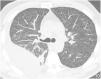

High-resolution computed tomography (HRCT) is the imaging method of choice for the evaluation and diagnosis of interstitial lung diseases because it confirms the presence of lung disease and establishes the correct diagnosis for associated complications. Nevertheless, the definitive diagnosis of these entities requires the imaging findings to be interpreted together with their clinical manifestations and histological confirmation. In this group of diseases, HRCT findings play a fundamental role, being especially important for avoiding unnecessary biopsies. For these reasons, clinicians need to be familiar with the basic radiologic patterns associated with this group of lung diseases: septal, reticular, nodular, ground-glass, cystic, and consolidations. This chapter describes the features of these patterns and ways that they can present, and it reviews some of the most common interstitial lung diseases, emphasizing the predominant radiologic patterns in each of them.